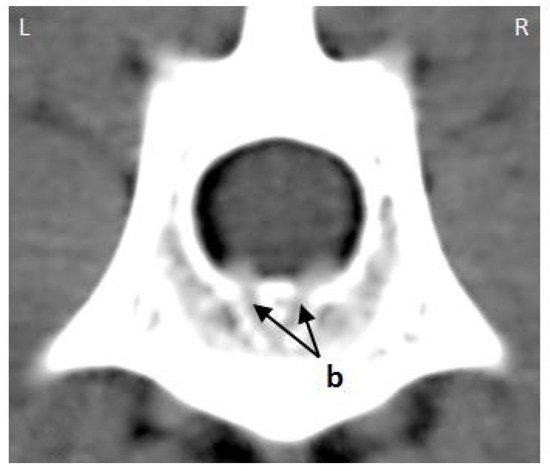

3.1. Internal Vertebral Venous Plexus